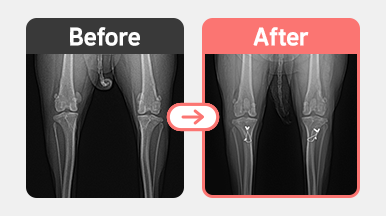

[슬개골 탈구 수술] 포메라니안 / 4살 / 양측 슬개골탈구 2기

[슬개골 탈구 수술] 요크셔테리어 / 5살 / 우측2기 좌측 3기

[슬개골 탈구 수술] 비숑 / 2살 / 양측 MPL (우 G3 / 좌 G2)

[슬개골 탈구 수술] 말티푸 / 1살 / 양측 MPL / 무릎 성형 + 인대 교정